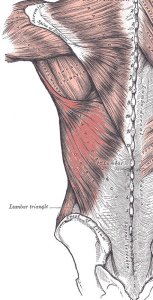

Latissimus dorsi: der Latissimus dorsi , der große seitliche Rückenmuskel, besteht meist (pars scapularis kann fehlen) aus 4 Teilen:

- pars vertebralis: entspringt am 7.-12. Brustwirbel

- pars iliaca: entspringt am hinteren Drittel des Beckenkamms und der fascia thoracolumbalis und

- pars costalis: Rippenanteil

- pars scapularis: Schulterblattanteil

Die 4 Teile setzen am hinteren oberen Oberarm an und wirken zusammen bei der lateralen Adduktion und auch frontalen Adduktion des Arms. Weiter ziehen sie die Schulterblätter nach hinten (Retraktion) und unten (Depression), wirken bei der forcierten Ausatmung (z.B. beim Husten) mit und bewirken, je nach Stellung des Arms mehr oder weniger stark eine Endorotation desselben.